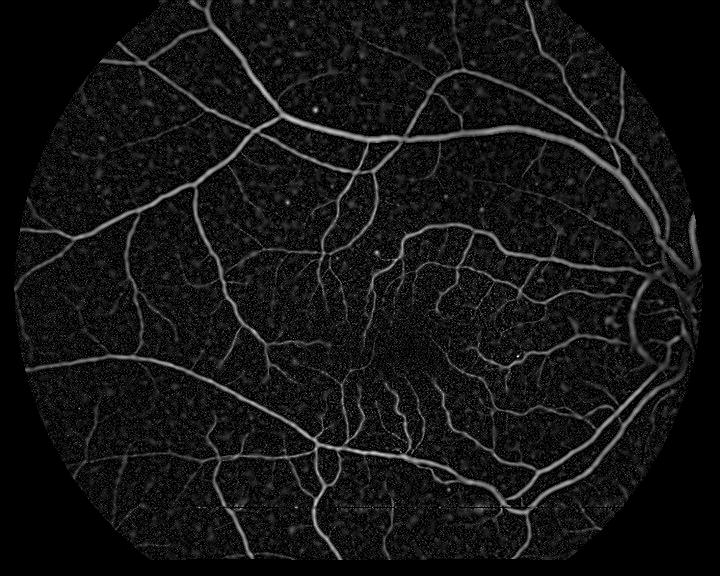

where m=1𝑚1m=1 for the angiography and m=1𝑚1m=-1 for the retinography, and subscript\lceil\cdot\rceil_{\emptyset} denotes the halfwave rectification. The rectification is used to avoid the negative Laplacian peaks outside the vessel regions so that only the vessel interiors are represented in the enhanced images. This results in a common representation for the retinography and the angiography, with enhanced vessel regions and the same intensity level pattern. Figure. 2 shows the result of the vessel enhancement operation applied to the retinography/angiography pair exposed in Fig. 1.

Refer to caption

Figure 2: Examples of the vessel enhancement operation applied to the multimodal image pair in Fig. 1: (a) result from retinography; (b) result from angiography.